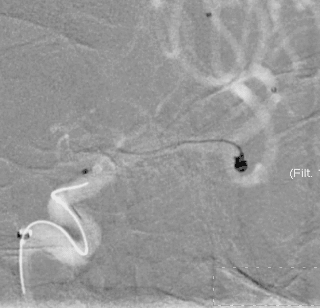

术前影像

栓塞过程

填塞第一枚Jasper®SS弹簧圈顺利;由于瘤囊较小,担心弹簧圈的稳定性,选择支架半释放后,顺利填入第2枚Jasper®SS弹簧圈。造影显示动脉瘤致密填塞,随后完全释放支架。

术后即刻影像